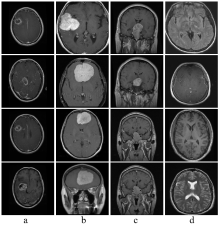

颅内肿瘤是一种严重的神经系统疾病,早期检测对提高患者生存率具有重要意义.然而,现有深度学习模型在颅内肿瘤图像分类任务中仍面临特征提取不足、模型复杂度较高以及类别不均衡等问题.为此,本研究提出了一种轻量化深度学习网络(AD-Net).该网络创新性地引入动态卷积机制,自适应调整滤波器响应,从而增强了对颅内肿瘤复杂、不均特征的表征能力;结合通道注意力机制,有效聚焦关键通道信息,进一步提升了分类的准确性与模型的可解释性.此外,本研究提出了结合二分类与三分类的训练策略,显著缩短了模型训练时间,降低了计算资源的需求,使其更适用于资源受限的医疗环境.在实验中,AD-Net在准确率、精确率、召回率、F1分数以及Kappa一致性系数等关键评价指标上均优于现有主流深度学习模型,验证了其在颅内肿瘤分类任务中的有效性与实际应用价值.

Abstract: Intracranial tumors represent a serious neurological disorder, and early detection is critical for improving patient survival rates. However, current deep learning models for intracranial tumor image classification often suffer from insufficient feature extraction, high model complexity, and class imbalance. To address these challenges, this study proposes a lightweight deep learning architecture, adaptive dynamic network (AD-Net). The network innovatively incorporates a dynamic convolution mechanism that adaptively adjusts filter responses, thereby enhancing the representation of complex and imbalanced tumor features. Additionally, the integration of a channel attention mechanism enables the model to focus on critical channel information, further improving classification accuracy and interpretability. This study also introduces a combined binary and ternary classification training strategy, which significantly reduces training time and computational resource requirements, making the model more suitable for resource-constrained medical settings. Experimental results demonstrate that AD-Net outperforms existing mainstream deep learning models in terms of accuracy, precision, recall, F1 score, and Cohen’s Kappa coefficient, confirming its effectiveness and practical value for intracranial tumor classification.